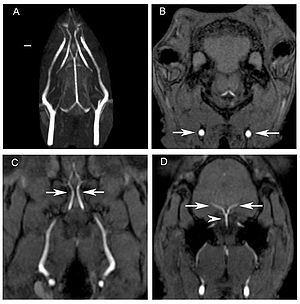

- 2.6 In Vivo Visualization of the Facial Nerve in Patients with Acoustic Neuroma using Diffusion Tensor Imaging-Based Fiber Tracking

Publication: J Neurosurg. 2016 Jan 1:1-8. PMID: 26722859 Authors: Song F, Hou Y, Sun G, Chen X, Xu B, Huang JH, Zhang J. Institution: Department of Neurosurgery, People's Liberation Army General Hospital, Beijing, China. Background/Purpose: OBJECTIVE Preoperative determination of the facial nerve (FN) course is essential to preserving its function. Neither regular preoperative imaging examination nor intraoperative electrophysiological monitoring is able to determine the exact position of the FN. The diffusion tensor imaging-based fiber tracking (DTI-FT) technique has been widely used for the preoperative noninvasive visualization of the neural fasciculus in the white matter of brain. However, further studies are required to establish its role in the preoperative visualization of the FN in acoustic neuroma surgery. The object of this study is to evaluate the feasibility of using DTI-FT to visualize the FN. Methods Data from 15 patients with acoustic neuromas were collected using 3-T MRI. The visualized FN course and its position relative to the tumors were determined using DTI-FT with 3D Slicer software. The preoperative visualization results of FN tracking were verified using microscopic observation and electrophysiological monitoring during microsurgery. Results Preoperative visualization of the FN using DTI-FT was observed in 93.3% of the patients. However, in 92.9% of the patients, the FN visualization results were consistent with the actual surgery. CONCLUSIONS DTI-FT, in combination with intraoperative FN electrophysiological monitoring, demonstrated improved FN preservation in patients with acoustic neuroma. FN visualization mainly included the facial-vestibular nerve complex of the FN and vestibular nerve. |